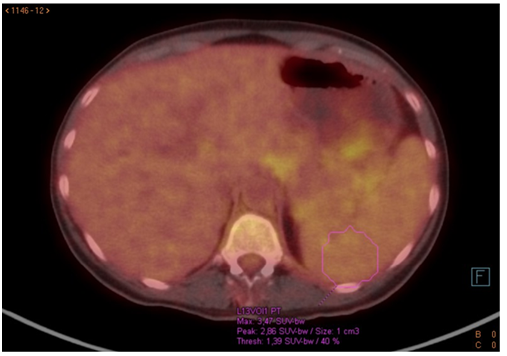

Also a TPE was taken out glandular involvement supra and, to a greater extent, infradiafrgamatics, highlighting an increase in retroperitoneal hyper metabolic density; as well as intestinal infiltration and right parotid doubtful. Probable splenic and medullary bone hyperreactivity with dubious right iliac focus. Moderate amount of normometabolic ascitic fluid.

Figure 8 Bone uptake by PET.

Figure 9 Splenic uptake by PET.

Figure 10 Retroperitoneal uptake by PET.